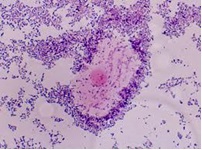

03:37 CH @ 21/06/2013Soi tươi bệnh phẩm dịch âm đạo, niệu đạo có thể phát hiện nấm men, trùng roi Trichomonas vaginalis, Gradnerella vaginallis và nhậnXét nghiệm soi trực tiếp chẩn đoán nấm gây bệnh

03:29 CH @ 21/06/2013Xét nghiệm nấm gây bệnh cũng tương tự như xét nghiệm vi khuẩn gây bệnh. Những bệnh nhân nghi ngờ bị nhiễm nấm được tiến hànhBệnh nhiễm giun kim